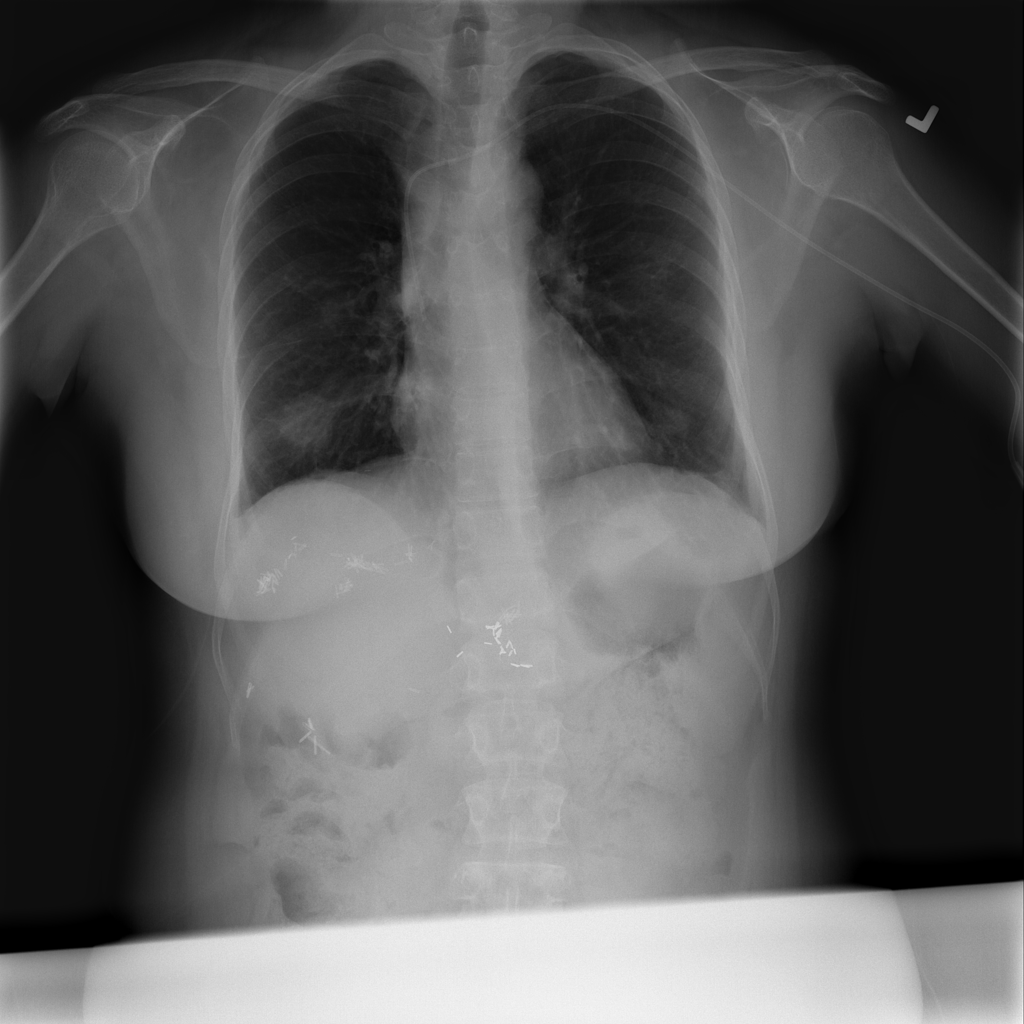

Showing up to 90 reference images for Nodule.

PAT-F3E7 · IMG-002Nodule

PAT-F3E7 · IMG-002

PA